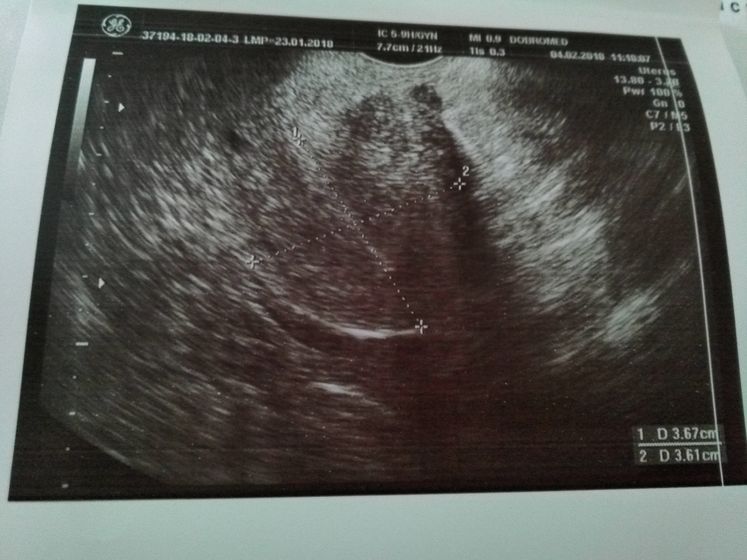

Поехали сегодня в пургу и вьюгу на УЗИ в Добромед(не в восторге) Сделали узи, рассказала что и как врачу, при осмотре было желтое тело, но как я поняла, не совсем то что нужно. В остальном все хорошо, матка, яичники все в норме. Критичного ни чего нет. Послали на ХГЧ завтра за результатом. Если есть, кто разбирается в заключении и в узи, буду рада информации. Тест все еще показывает //